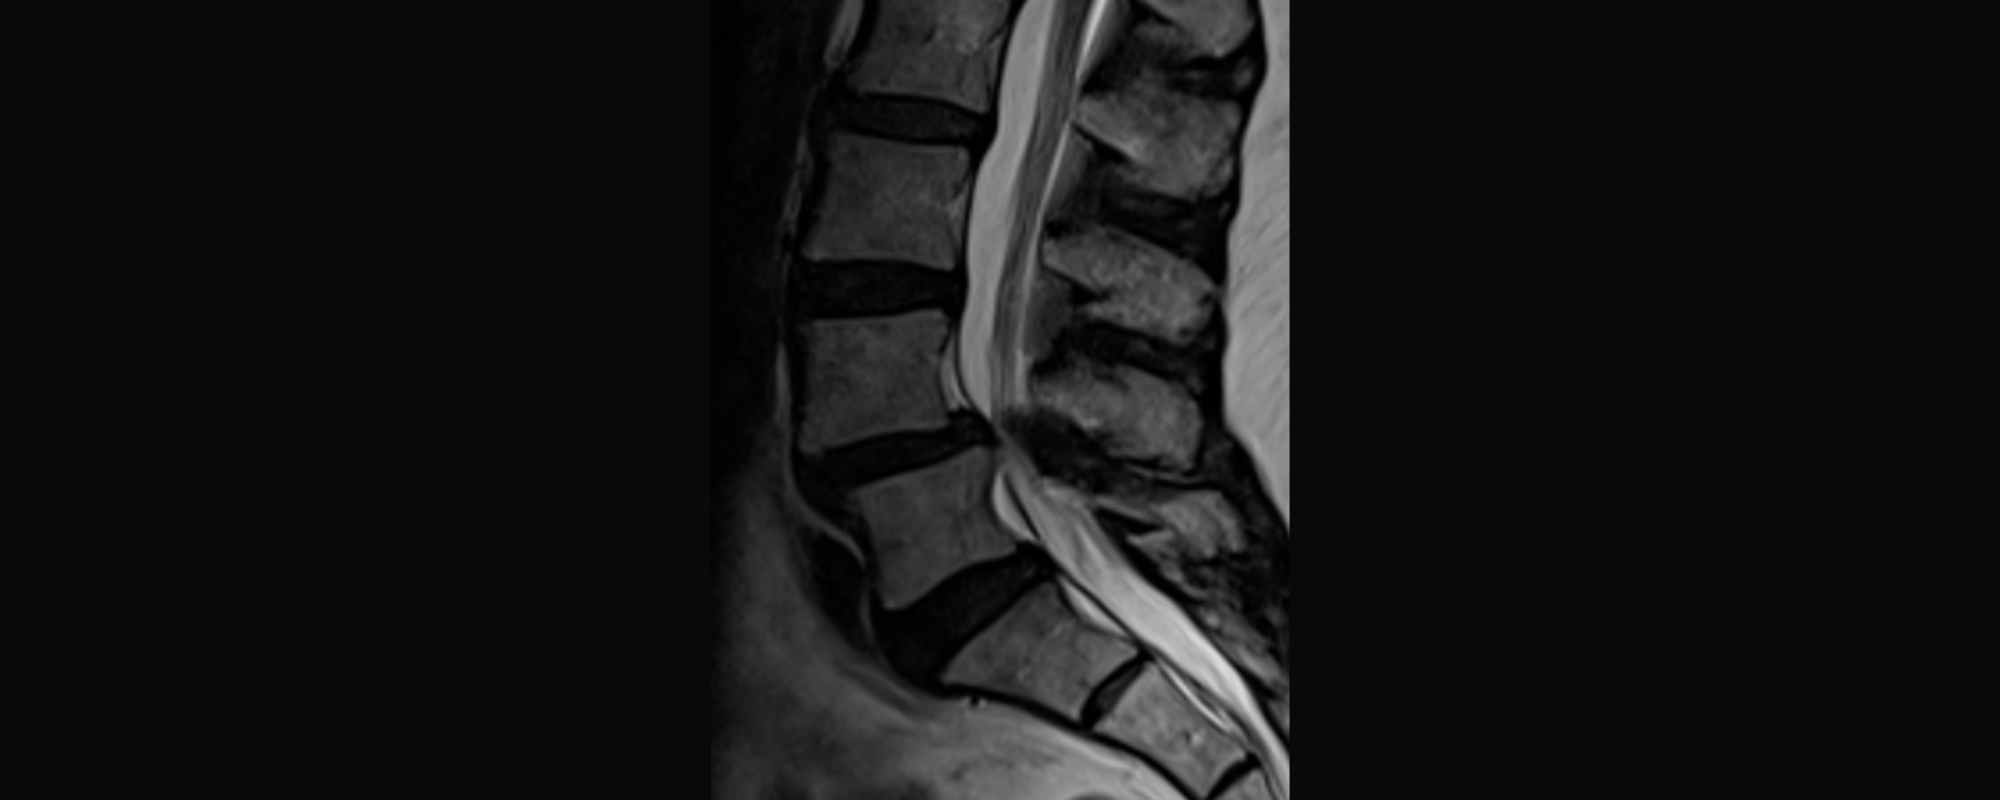

Omurilik Kanal Daralması (Spinal Stenoz) Nedir?

Bel Kayması Nedir?

Boyun Fıtığı Nedir?